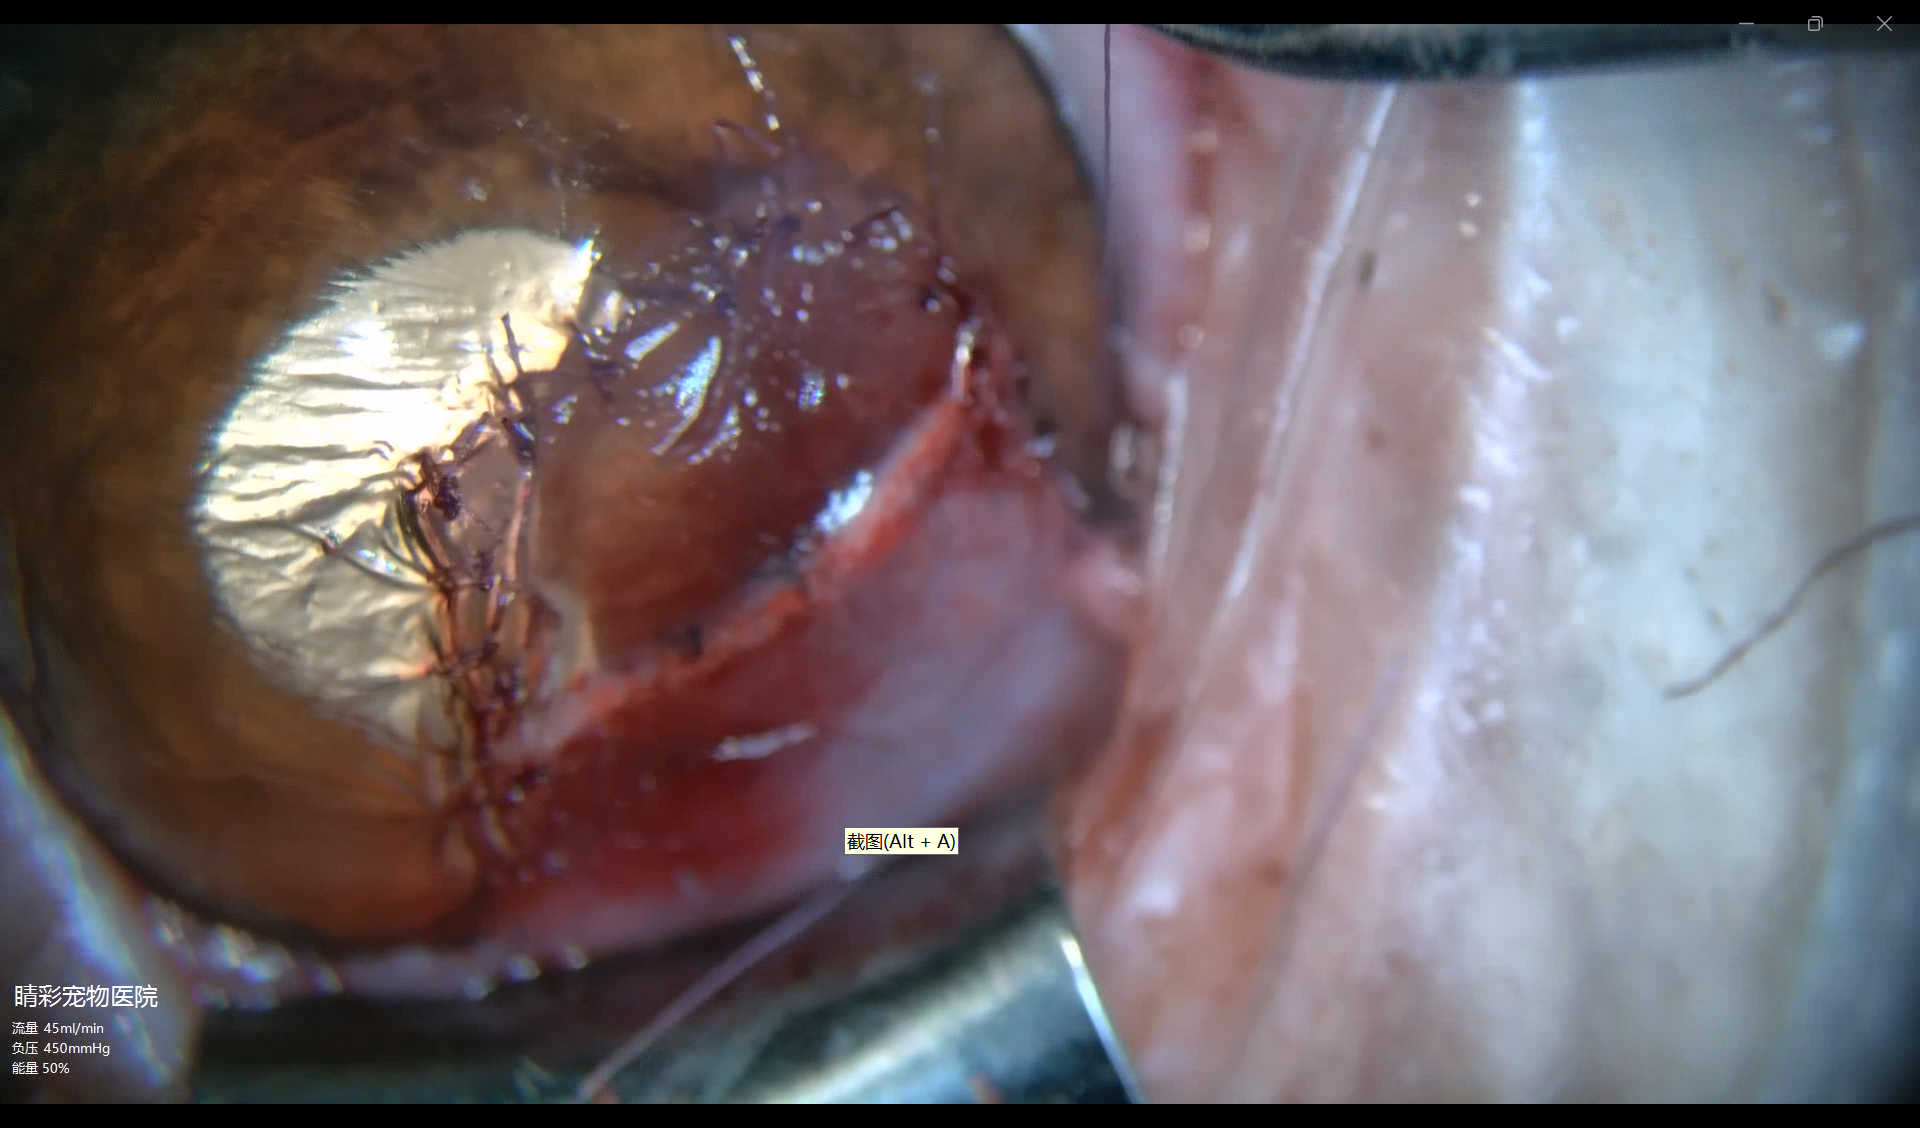

4.1、术中突发情况:

手术眼os,板层切除腐骨灶过程中由于病灶深度过深,发生穿孔(图4-1),随即更改手术术式为角膜sis补片加角结膜板层移动术(图4-2)术后佩戴角膜接处镜,眼睑板关闭转内科用药

图4-1 术中发生角膜穿孔,前房塌陷

图4-2缝合完成的sis补片加角结膜板层